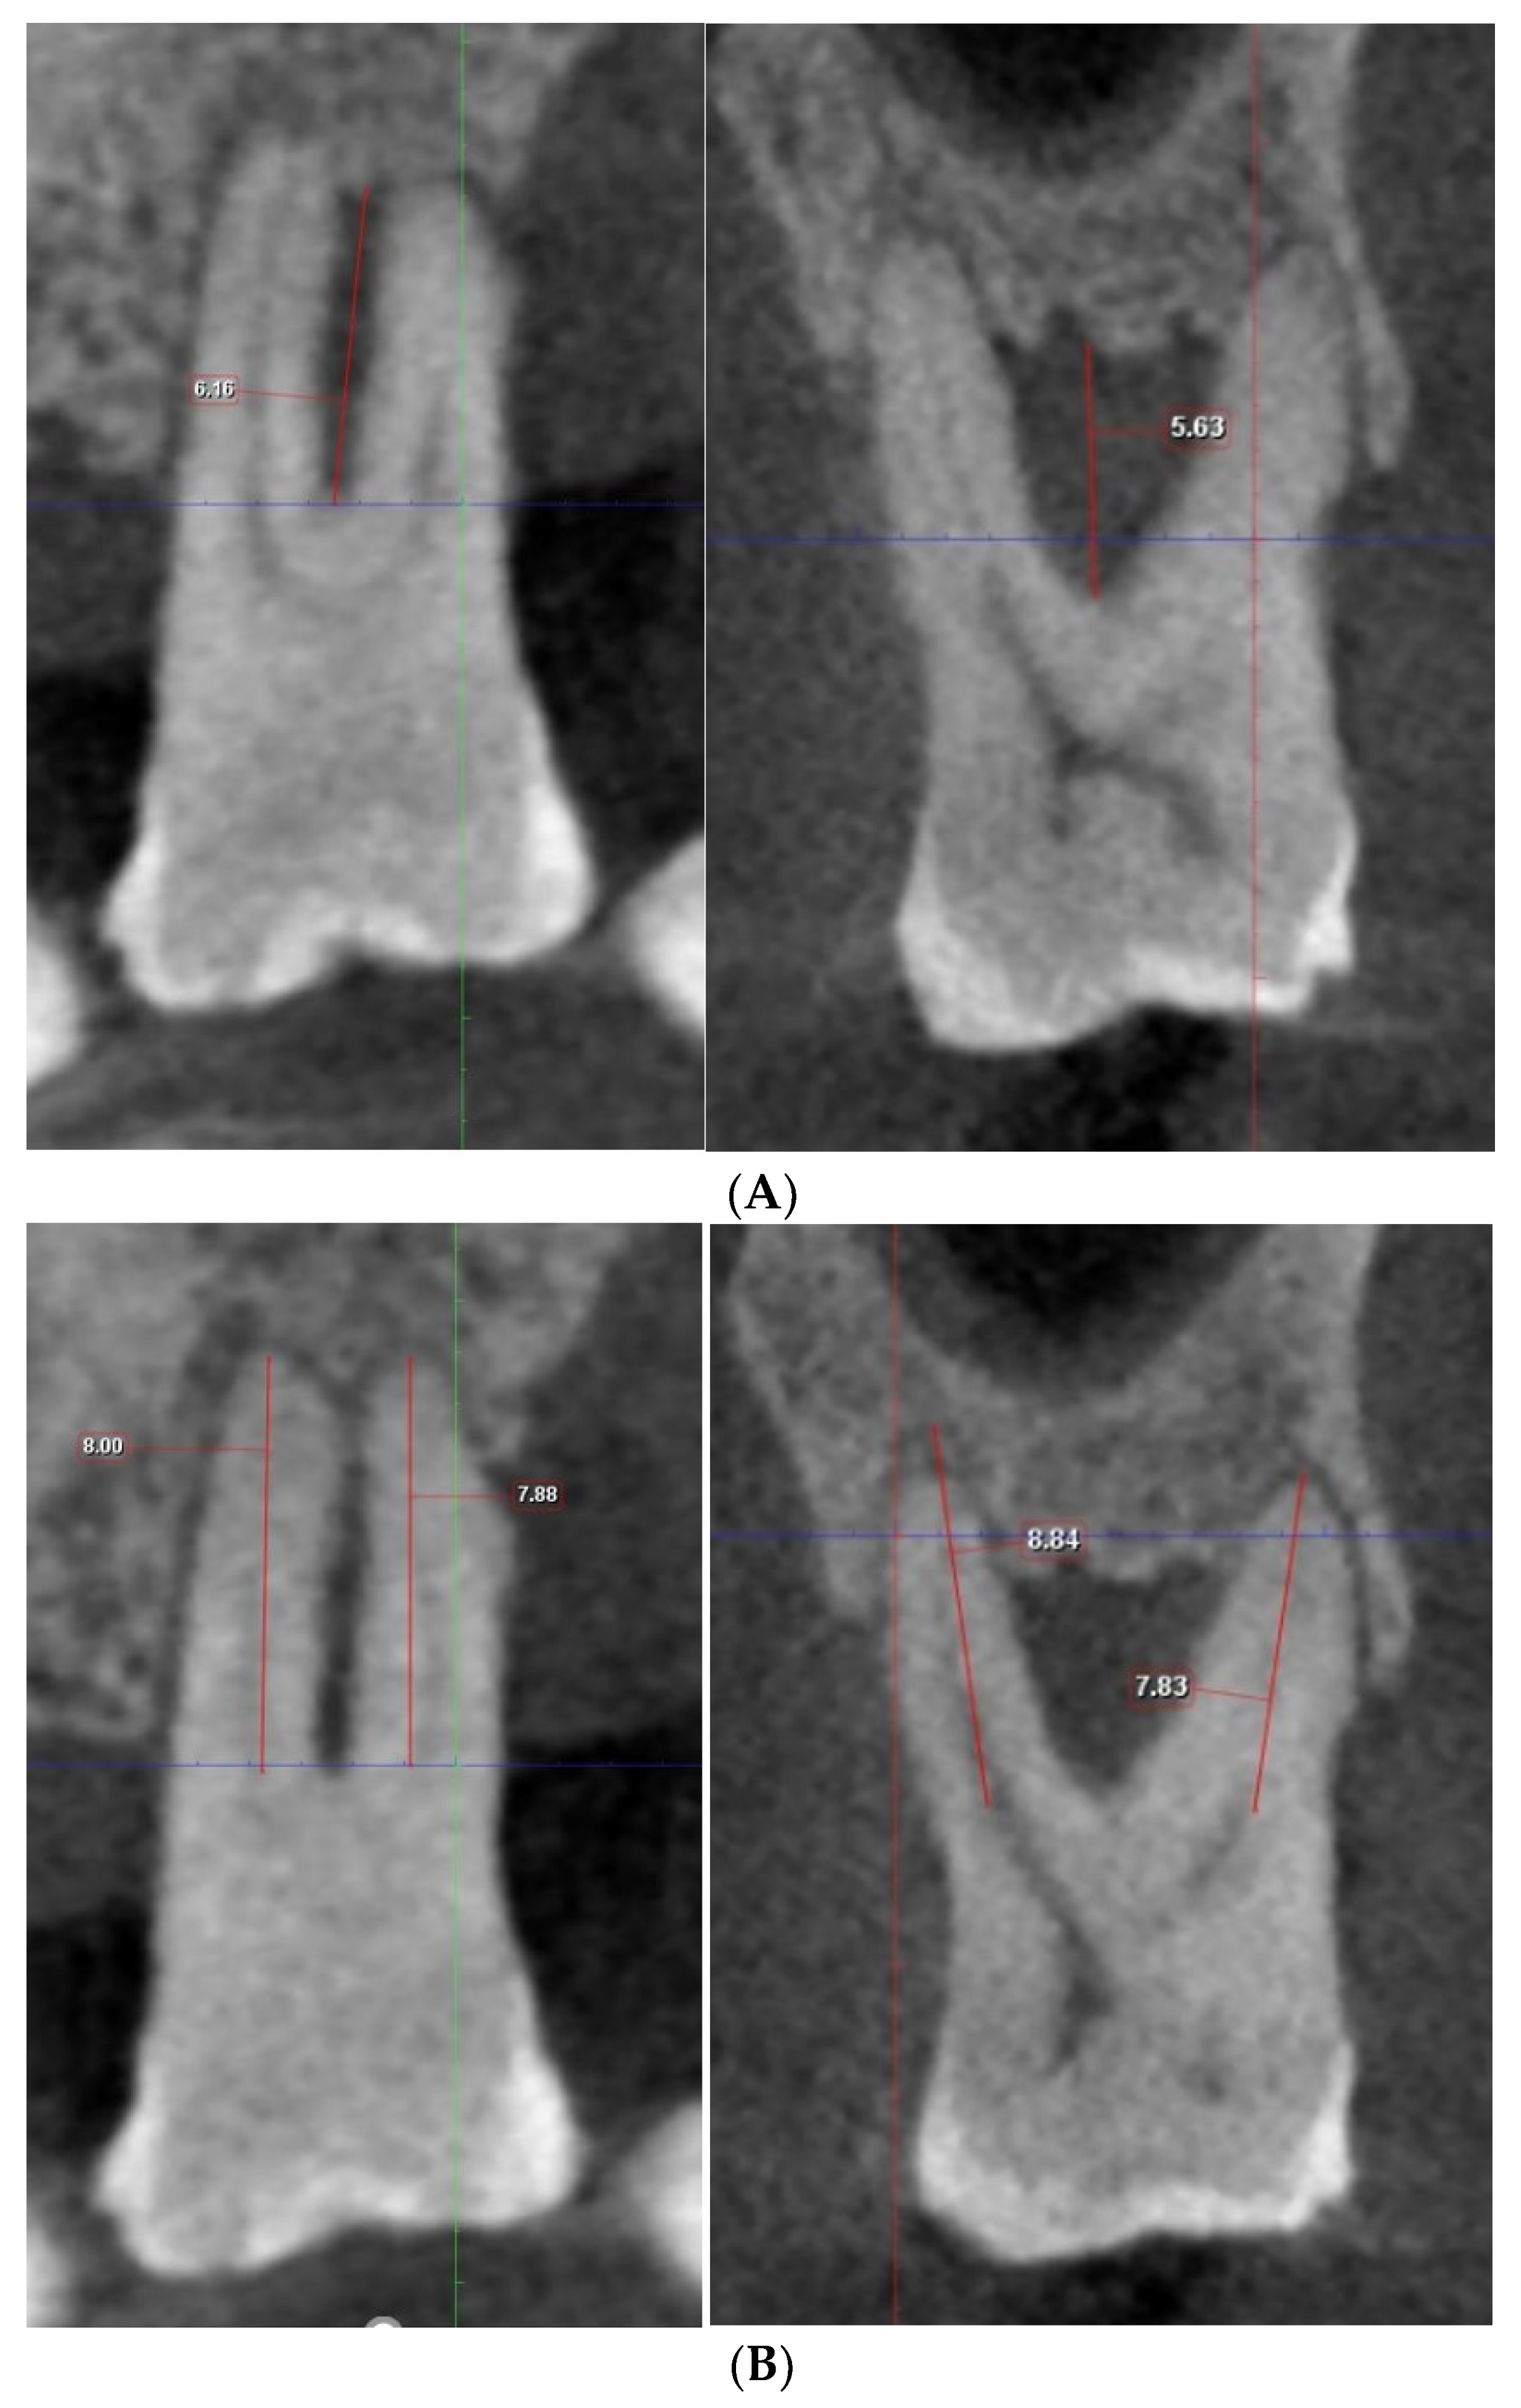

Figure 2. (A) Measurement of vertical depth of furcation and root length on Romexis (Planmeca). (B) By toggling the CBCT along the adjusted axis, the maximal vertical distance from the furcation fornix to the base of the defect and the length of the shorter root bounding the furcation were measured.

CBCT DICOM files of the molars included were imported into the Romexis Viewer (Version 6.1, Planmeca, Helsinki, Finland) and analysed by two calibrated investigators (P.M.L. and A.W.K.Y.). The horizontal furcation involvement, as shown in the clinical charting, was first confirmed on the CBCT images. An assessment of the vertical bone loss in the furcation was then performed. The CBCT viewer axis was first aligned along the long axis of the tooth at the sagittal section and coronal section. At the axial section, the sagittal and coronal planes were adjusted to intersect the canal orifices of the two roots bounding the concerned furcation involvement (Figure 1). The sites with a deeper vertical furcal depth were chosen. The measurement was made to the nearest 0.1 mm using the linear measurement tool on the Romexis Viewer. The tooth was classified according to the modified vertical furcation subclassification and served as the gold standard. By toggling the CBCT along the adjusted axis, the maximal vertical distance from the furcation fornix to the base of the defect and the length of the shorter root bounding the furcation were measured. The exact measurement was repeated on the other furcation entrance(s) if the subject tooth had more than one class II horizontal FI in the maxillary molars (Figure 2).